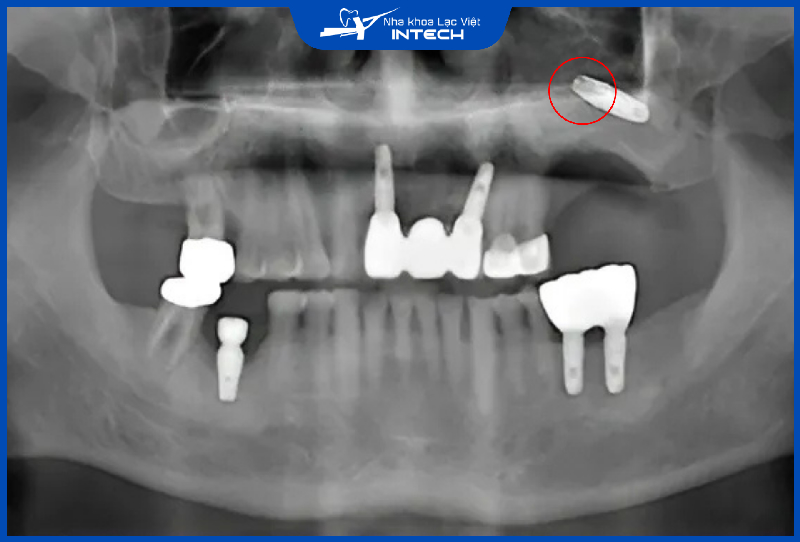

2.2. Rủi ro tổn thương ống thần kinh răng dưới và thủng xoang hàm

Cấy ghép Implant không đúng cách có thể gây tổn thương đến các cấu trúc giải phẫu quan trọng như ống thần kinh răng dưới hoặc xoang hàm ở hàm trên. Những biến chứng này thường bắt nguồn từ việc bác sĩ không thực hiện đầy đủ khảo sát tình trạng xương hàm và các cấu trúc liên quan trước khi tiến hành phẫu thuật

Điều này có thể do thiếu trang thiết bị chẩn đoán hiện đại hoặc do bác sĩ chưa có đủ kinh nghiệm và chuyên môn trong lĩnh vực cấy ghép Implant. Các biến chứng thường xảy ra nhiều hơn tại các cơ sở nha khoa không đảm bảo chất lượng.

Ở hàm dưới, tổn thương ống thần kinh răng dưới có thể dẫn đến các hậu quả nghiêm trọng. Trong trường hợp nhẹ, cô chú/anh chị có thể cảm thấy tê bì hoặc mất cảm giác tạm thời ở vùng môi và mô xung quanh. Tuy nhiên, khi tổn thương nghiêm trọng hơn, cô chú/anh chị có thể phải chịu đựng tình trạng đau kéo dài, mất cảm giác vĩnh viễn hoặc khó phục hồi cảm giác ăn nhai ban đầu. Vì vậy, lời khuyên cho cô chú/anh chị là hãy tìm hiểu kỹ trồng implant là gì trước khi quyết định thực hiện nhé!

Nếu bác sĩ cắm Implant chạm vào ống thần kinh hàm dưới có thể gây tê bì, đau nhức hoặc mất cảm giác tạm thời, vĩnh viễn

Tương tự, ở hàm trên, biến chứng thủng xoang hàm xảy ra khi trụ Implant được đặt quá sâu hoặc không tính toán chính xác chiều dài. Đây là một trong những nguyên nhân khiến nhiều người băn khoăn cắm Implant có nguy hiểm không. Biến chứng này có thể gây viêm xoang hàm mãn tính, do vi khuẩn từ vùng miệng xâm nhập qua vết thủng, dẫn đến đau nhức kéo dài ở vùng má và mũi. Tình trạng này không chỉ gây ảnh hưởng sức khỏe mà còn làm tăng nguy cơ đào thải trụ Implant, vì môi trường xoang hàm không phù hợp để tích hợp xương với trụ.

Nếu cắm Implant sai lệch gây thủng xương hàm có thể gây viêm xoang mãn tính, đồng thời đào thải trụ Implant